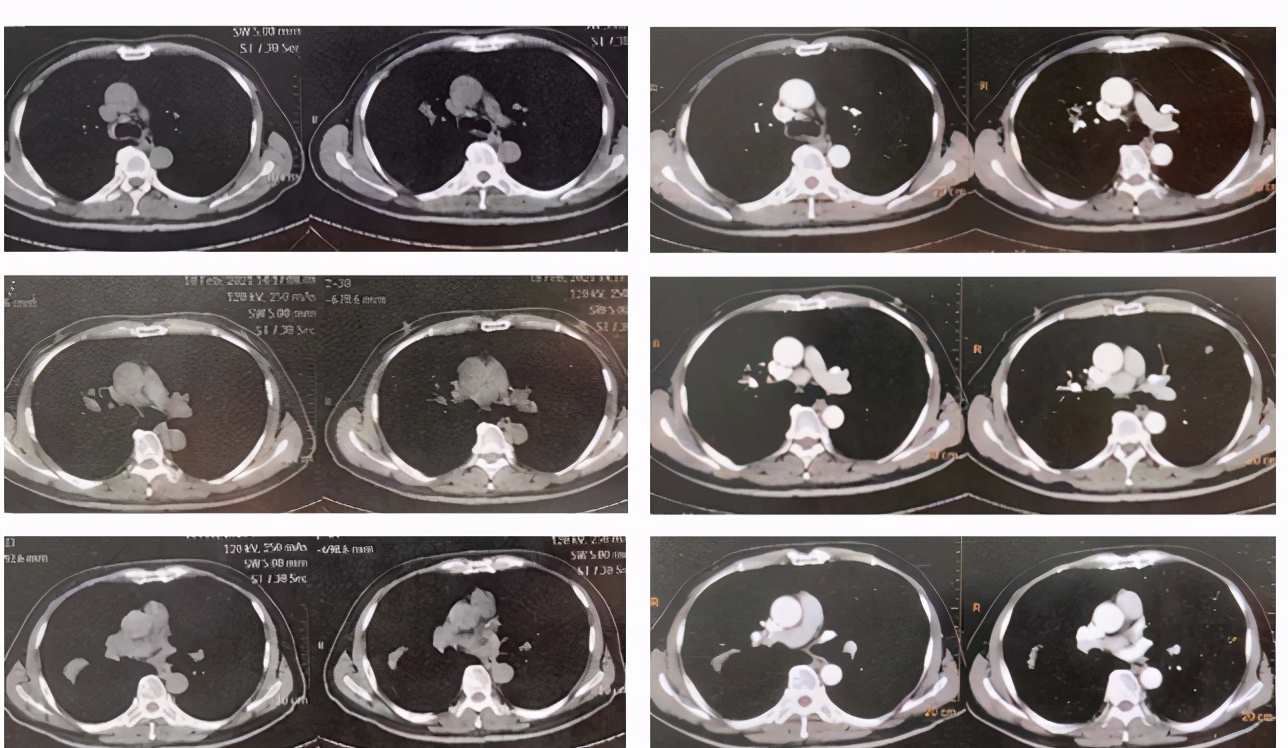

1年前肺CT(2020.3.12)

本次发病时肺CT(2021.2.18)

外院治疗后肺CT(2021.3.5)

1年前肺CT和发病时肺CT比较:

外院治疗前后肺CT比较:

黎庶教授(放射科)点评: 该患者的右肺门可见一团片影,其内可见正常走形的支气管,右肺上叶后段临近叶间胸膜处又可见一团片影,类圆形,边缘有毛刺,周围类似有晕征,除此之外肺内还可见多发散在的结节,边缘不规则。上述病灶经抗炎治疗没有改善,似乎有所加重。根据目前这些资料,无法确定感染还是非感染,一元论还是两元论,但肝癌肺转移肯定不是,因为肺内转移瘤不会形成大片状的改变,影像学不支持肝癌肺转移。肺CT改变更倾向于非感染,病灶沿支气管血管束旁和胸膜下分布,是多发的多种形态的,MALT淋巴瘤有这种特点,除此之外,炎性肌纤维母细胞瘤也有这种特点,血管炎、肉芽肿性病变也可出现。肺CT病变还有一个特点是既有实质改变又有间质改变,感染性疾病中TB、NTM和隐球菌都可以出现这种影像学改变。将肺脏和肝脏结合在一起分析,淋巴瘤可以同时多器官受累,风湿免疫系统疾病也可能。

激素治疗前后肺CT